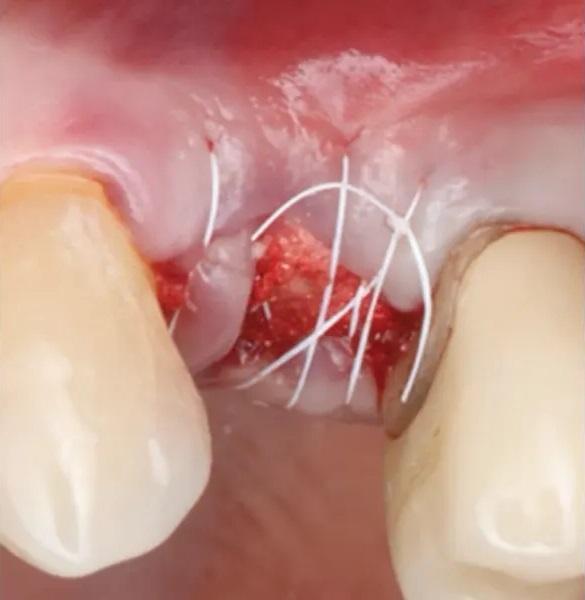

Фото 9. Пробка из ксеногенно-аллопластического биоматериала помещена в лунку, и наложен матрацный шов из ПТФЭ.